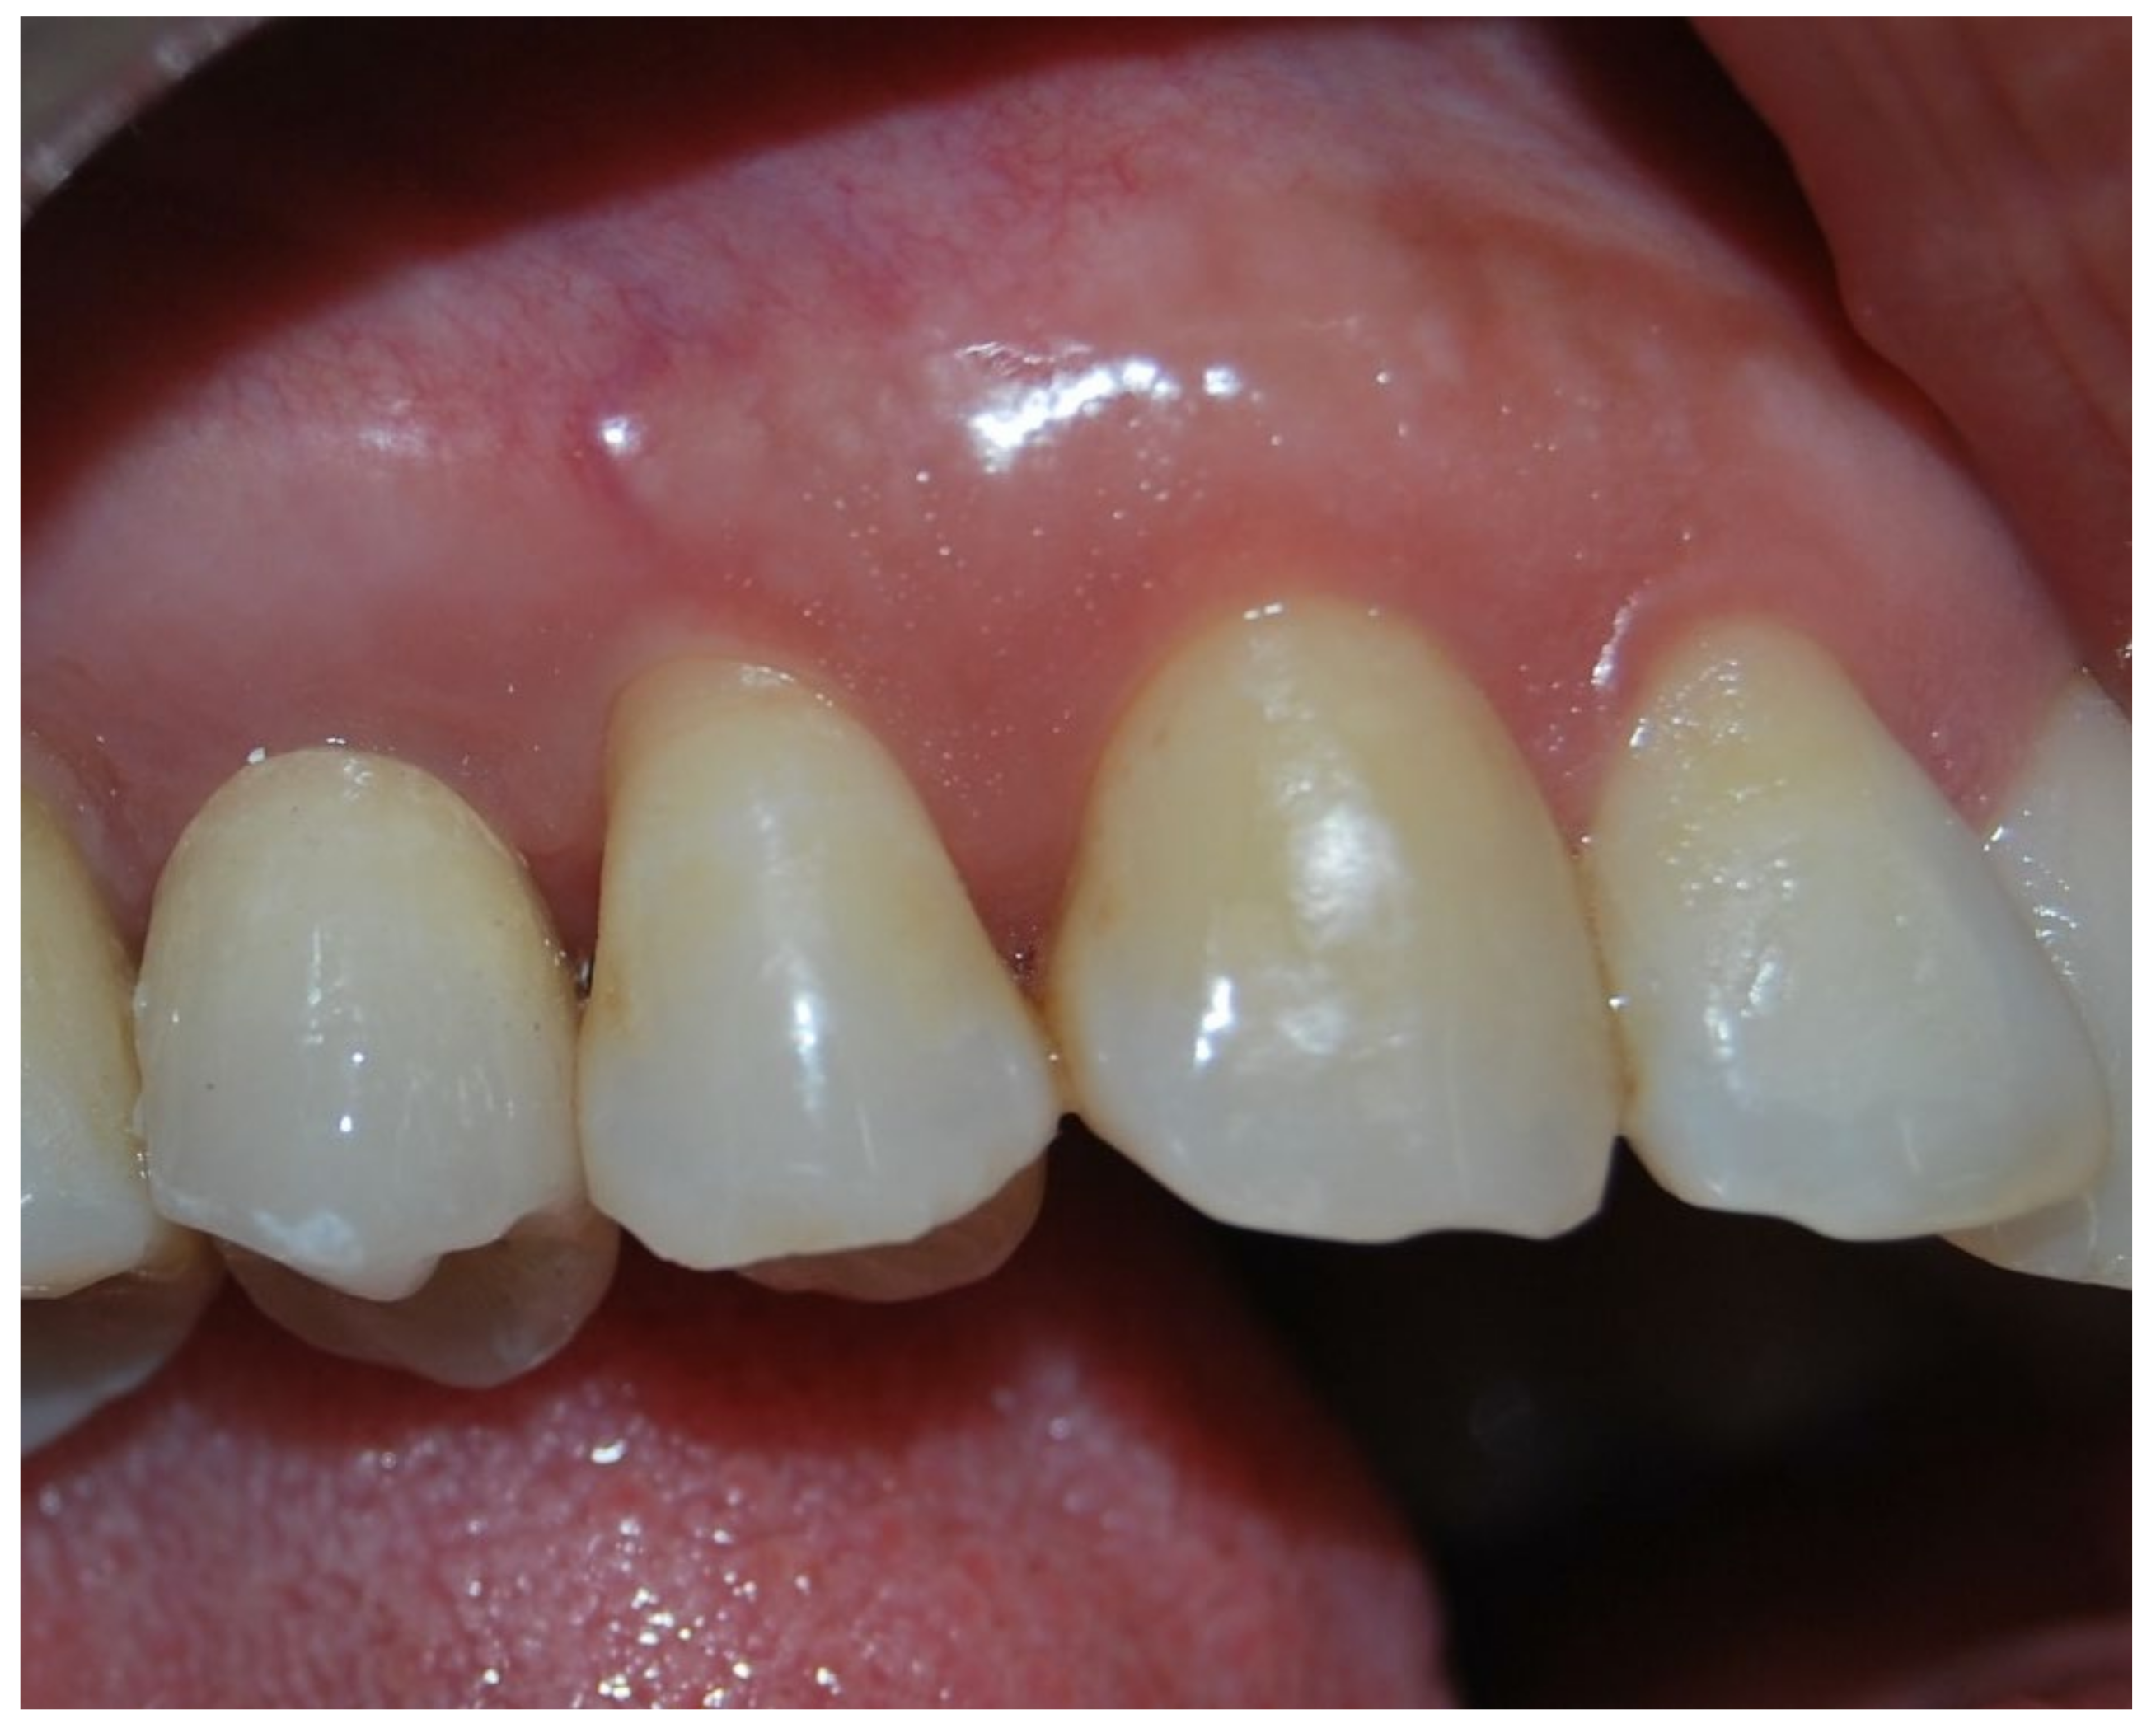

3. Results